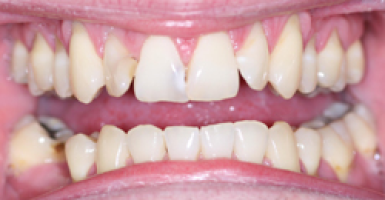

Invisalign

Before

After